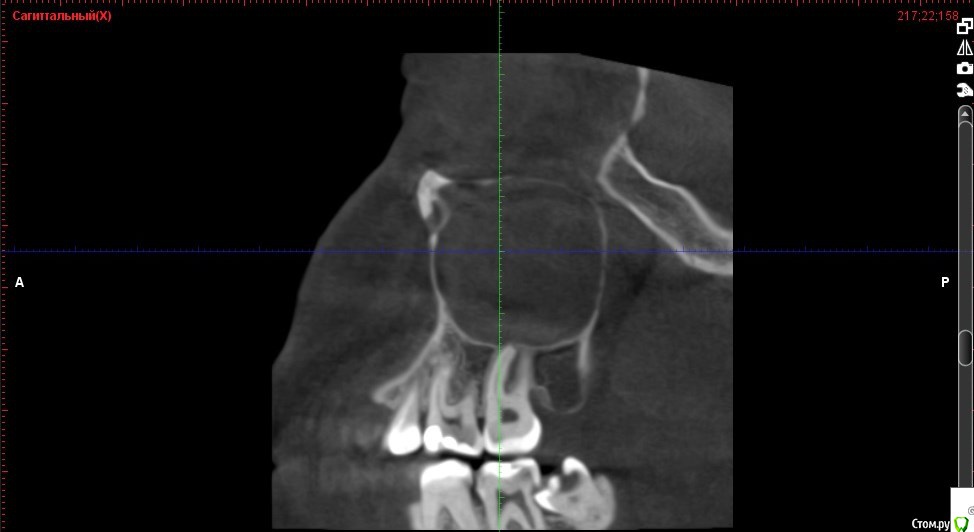

Verasss Опубликовано 8 октября, 2016 Автор Поделиться Опубликовано 8 октября, 2016 КТ от 08.09. Извините, что в таком виде, надо менять ОЗУ. Ссылка на комментарий

DmitrySH Опубликовано 8 октября, 2016 Поделиться Опубликовано 8 октября, 2016 В таком виде КТ малоинформативно. Но гайморита нет. Ссылка на комментарий

Verasss Опубликовано 28 октября, 2016 Автор Поделиться Опубликовано 28 октября, 2016 Добрый вечер! Ещё раз попытаюсь прикрепить скриншоты КТ от сентября. Если качество совсем не устраивает, подскажите, пожалуйста, какие сделать снимки?К сожалению, программа не позволяет вывести снимки на полный экран и заскриншотить в более хорошем качестве. Ссылка на комментарий

Verasss Опубликовано 28 октября, 2016 Автор Поделиться Опубликовано 28 октября, 2016 еще снимки Ссылка на комментарий